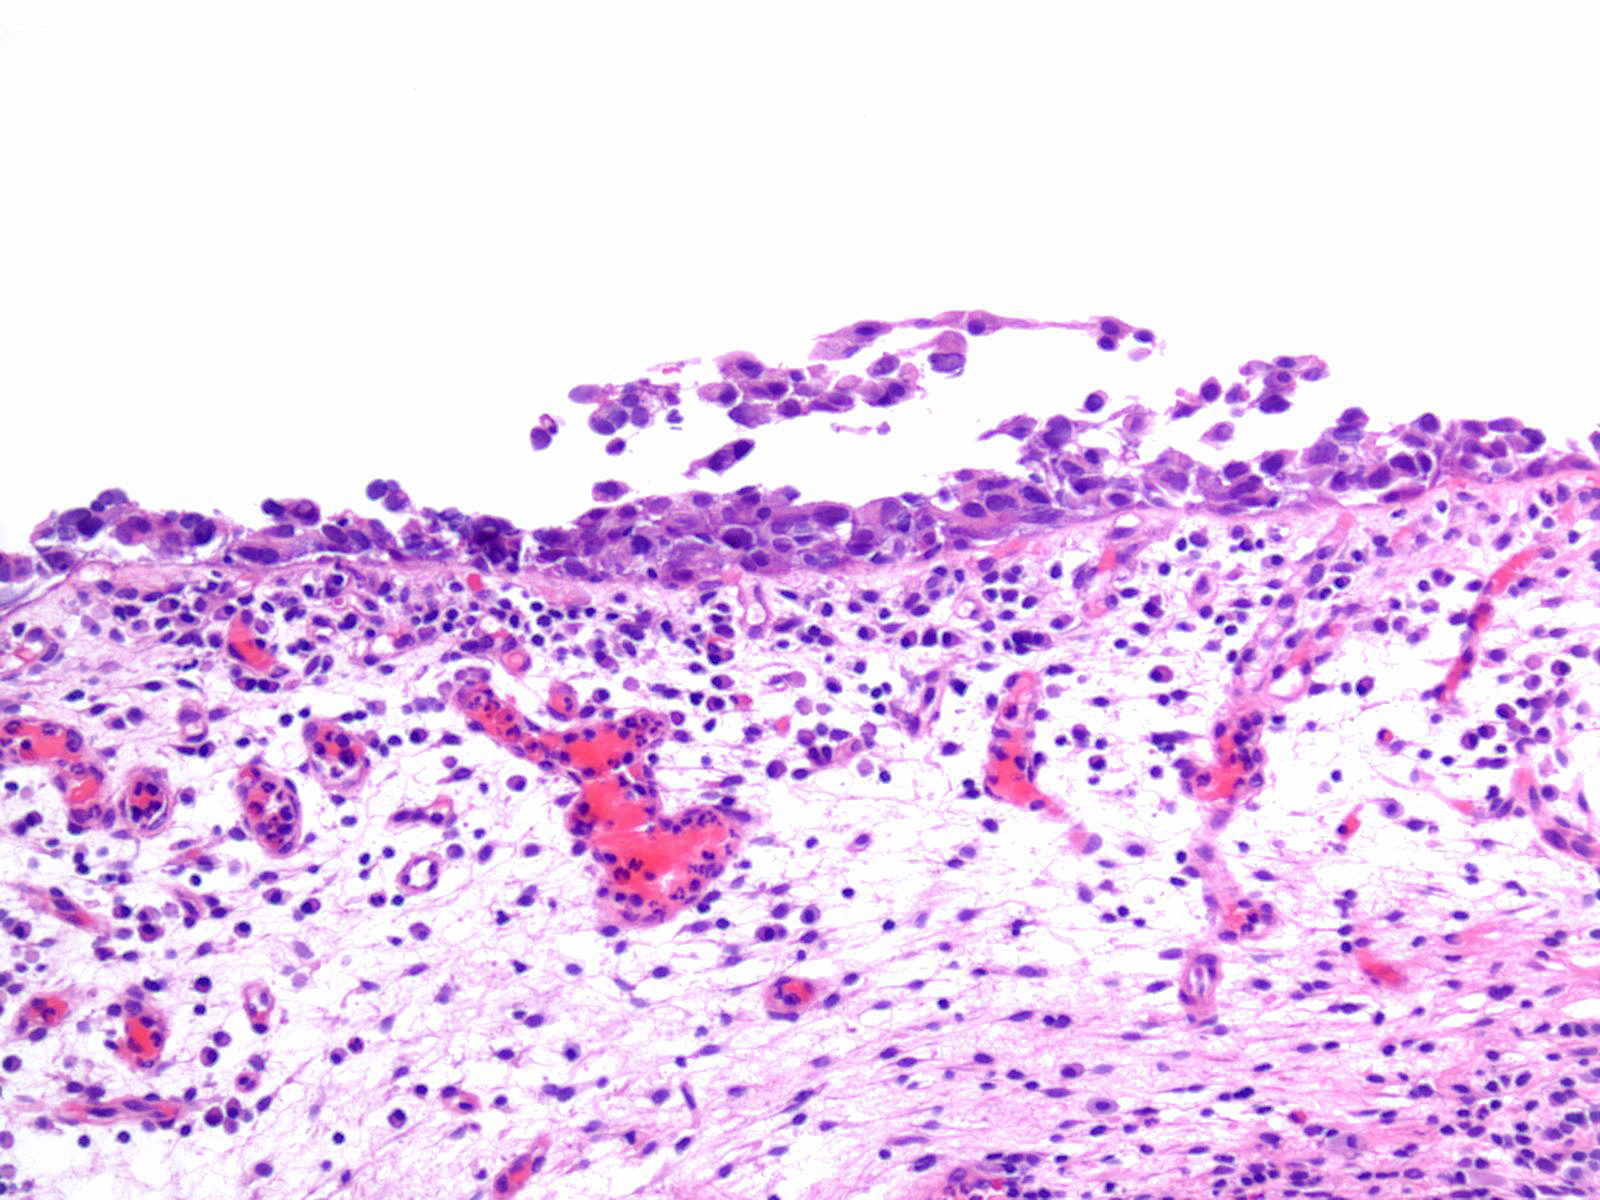

Consensus grade: Carcinoma in situ (CIS)

Lesion shows marked variation in nuclear size, shape and chromatin. Architecturally, cells appear irregularly clustered and the epithelium is disorganized.